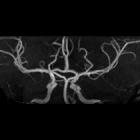

azygos anterior cerebral artery

An azygos anterior cerebral artery is an uncommon to rare variant of the circle of Willis where the two A1 segments of the anterior cerebral artery (ACA) join to form a single trunk. As a result, there is no anterior communicating artery. This organization is similar to that seen in lower primates .

As there is frequent hypoplasia of the anterior communicating artery and supply of the medial surface of the hemispheres by contralateral ACA branches, confirmation of an azygos ACA can be difficult on angiography . Cross compression views can be helpful.